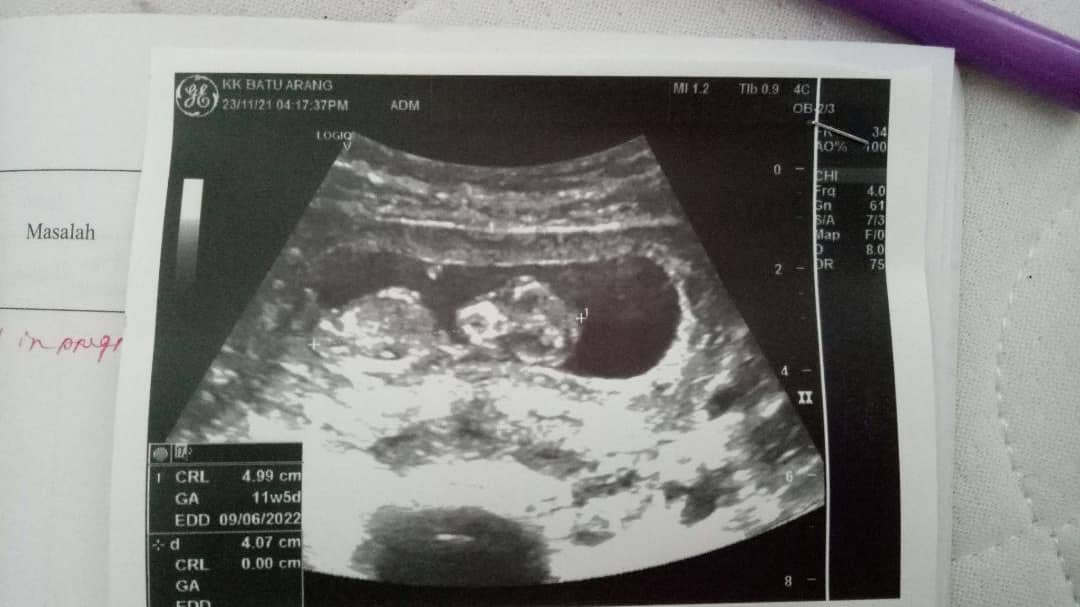

October | Disahkan hamil anak pertama

Nikmat yang terindah dalam hidup bila rahim dihuni oleh malaikat kecil. Lama juga menunggu kehadiran malaikat kecil ni, macam-macam dah fikir sehingga lah cuba berikhtiar dengan Efferty, Alhamdulillah rezeki dari Allah nak bagi zuriat asbab dari Efferty.

Akan dijaga anugerah Allah ni dengan sebaik-sebaik nya. Semoga zuriat ini menjadi khalifah Allah yang berbakti kepada ibu bapa, agama dan disenangi oleh semua orang disekeliling nya.